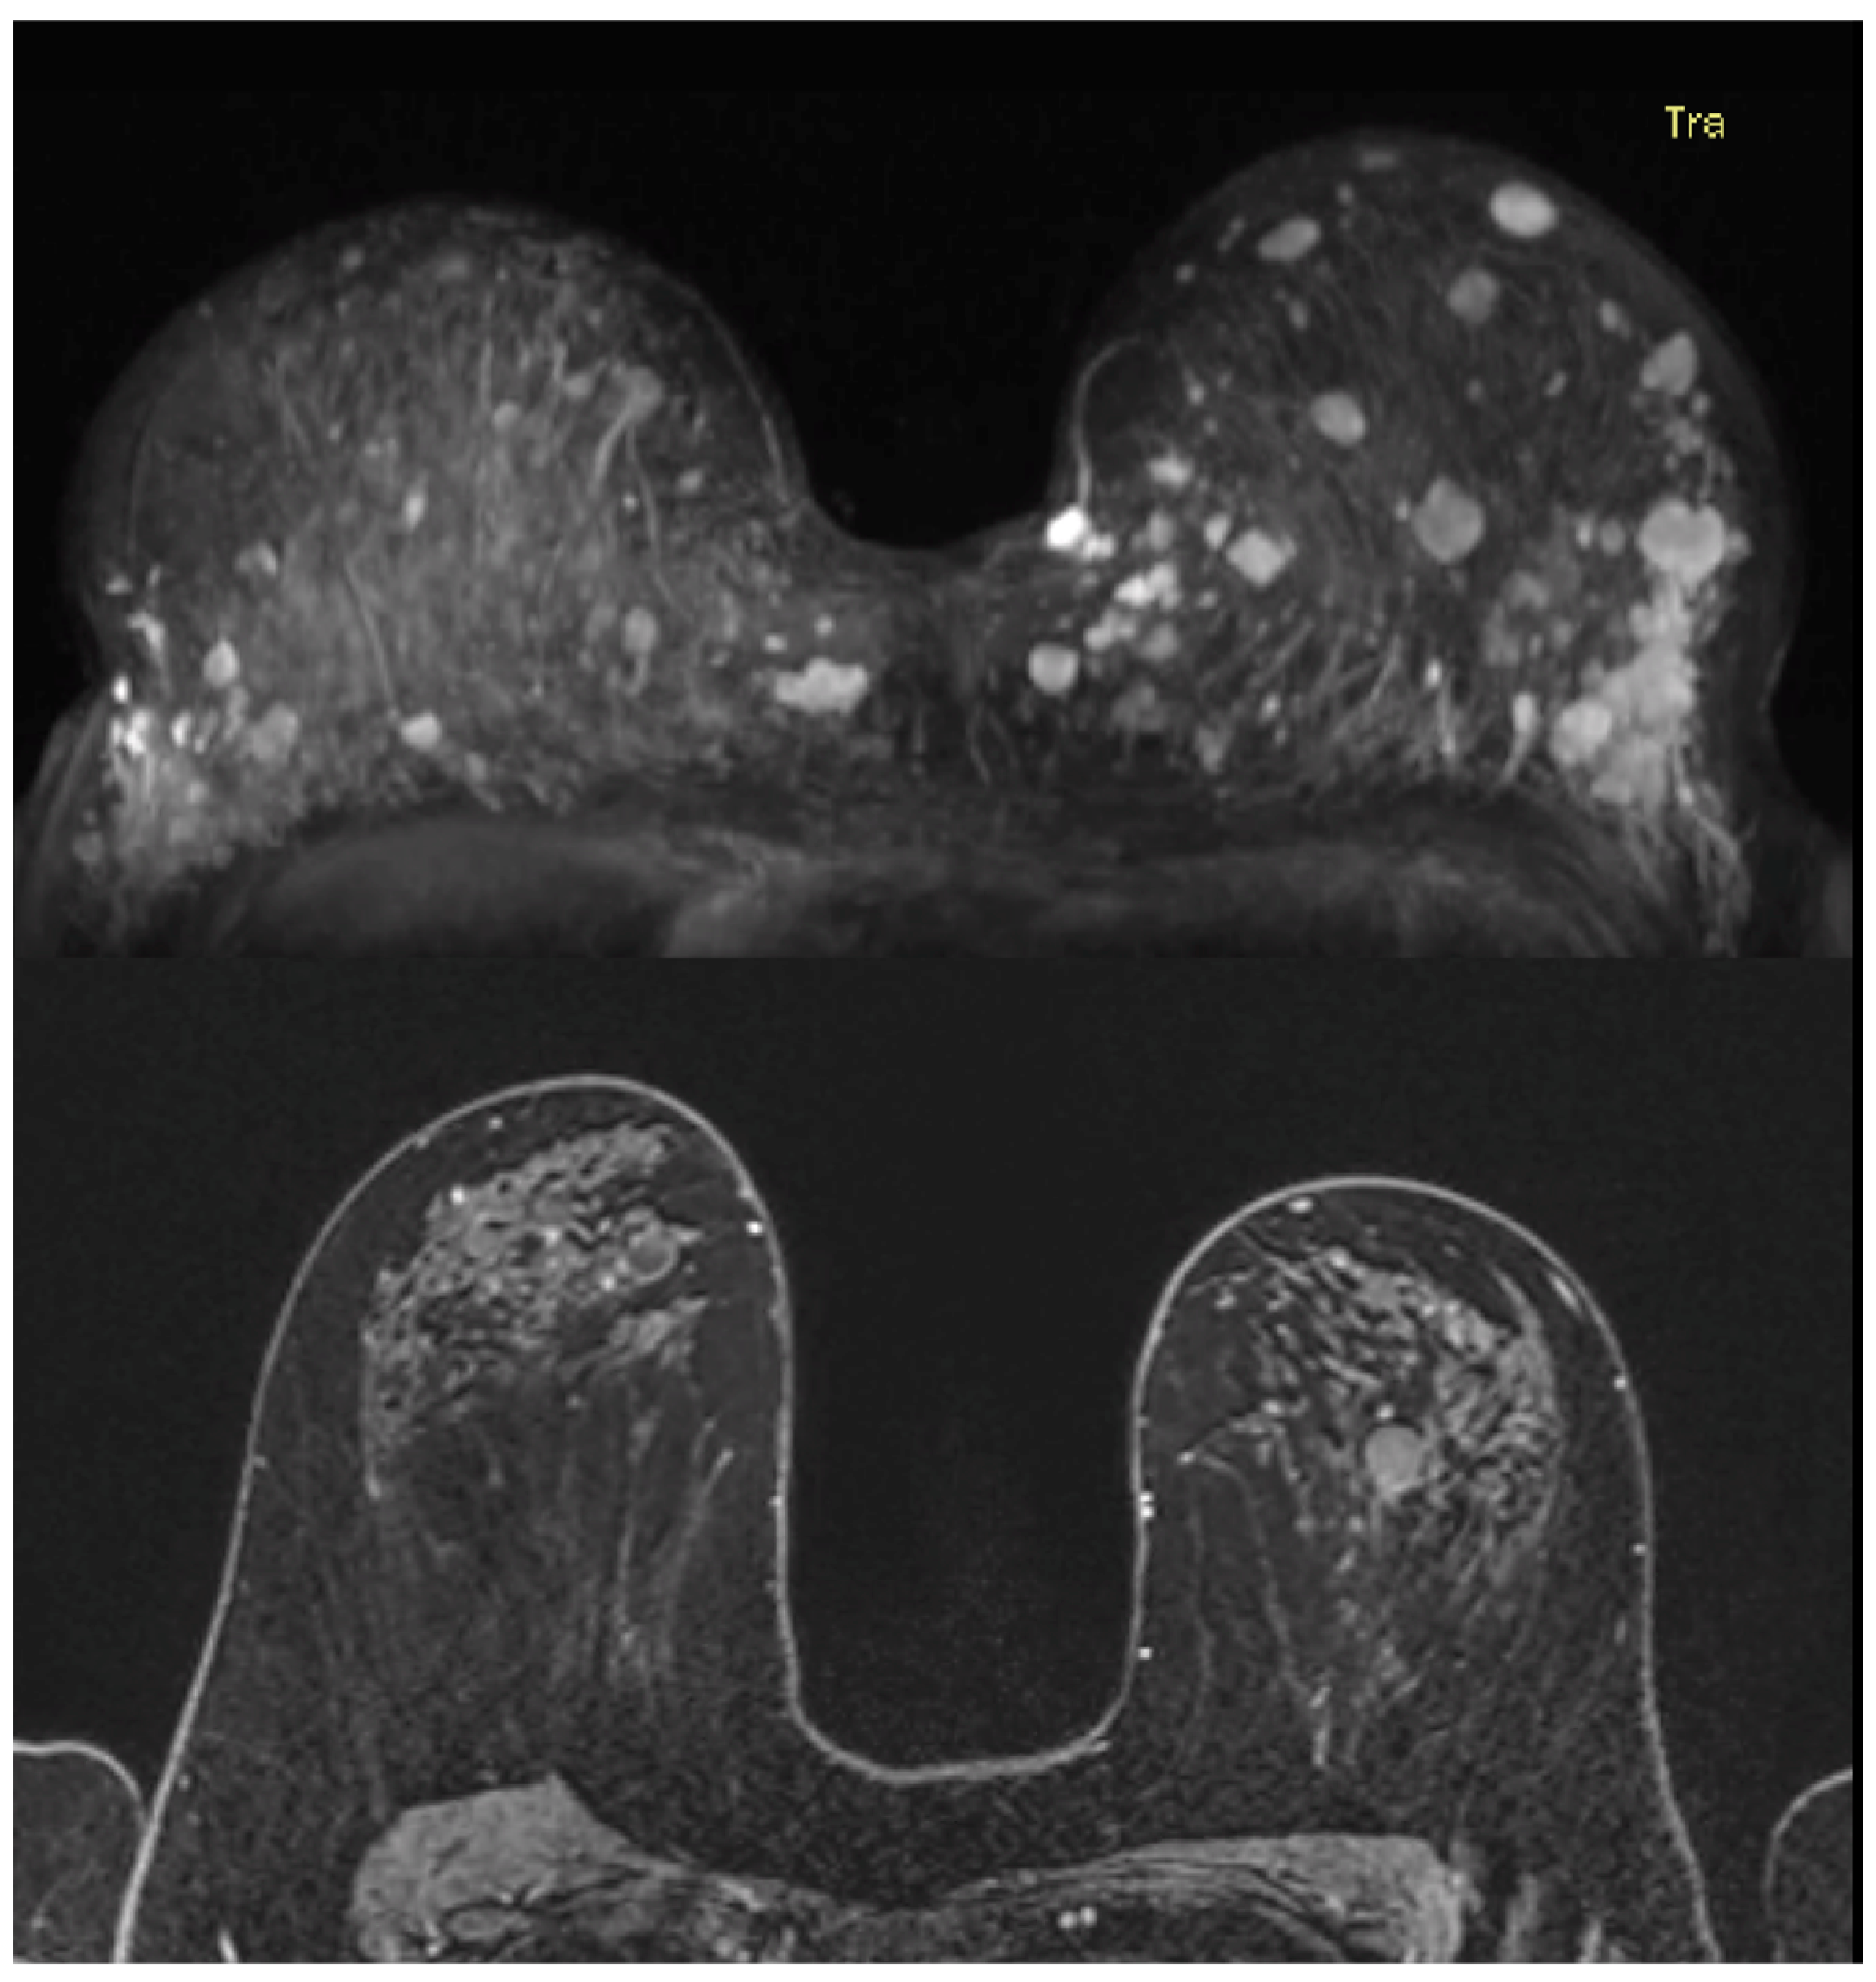

3.4. Imaging Features and Corresponding Pathology Outcome of Benign Breast Lesions

| Features | Benign Breast Lesions (N = 29) Described at MRI Examinations (N = 14) | |

|---|---|---|

| Lesion type | ||

| Focus | 2 | |

| Mass | 25 | |

| Shape | Round | 9/25 |

| Oval | 8/25 | |

| Irregular | 8/25 | |

| Margins | Circumscribed | 20/25 |

| Irregular | 5/25 | |

| Enhancement | Homogeneous | 1/25 |

| Heterogeneous | 15/25 | |

| Dark internal septations | 9/25 | |

| Non-mass enhancement | 2 | |

| Distribution modifiers | Focal area | 1/2 |

| Regional | 1/2 | |

| Internal enhancement | Heterogeneous | 2/2 |

| Kinetic curve assessment: initial phase 1 | Slow | 13/27 |

| Medium | 8/27 | |

| Fast | 6/27 | |

| Kinetic curve assessment: delayed phase 1 | Persistent | 11/27 |

| Plateau | 13/27 | |

| Washout | 3/27 | |

| Type of benign breast lesion | Fibroadenoma | 13/29 |

| Fybrocystic changes | 5/29 | |

| Adenosis | 4/29 | |

| Fibrosis/sclerosis | 3/29 | |

| Radial scar | 3/29 | |

| Intraductal papilloma | 1/29 |